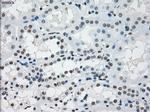

PRKY Monoclonal Antibody (OTI3E10), TrueMAB™

A group of proteins that are intimately involved in this process are the serine/ threonine (Ser/Thr) protein kinases. PRKY (protein kinase, Y-linked) and PRKX (protein kinase, X-linked) are members of the Ser/Thr protein kinase family, both of which belong to the subfamily of cAMP-dependent kinases. Encoded by a gene that is located near the pseudoautosomal region on chromosome Y, PRKY contains one protein kinase domain through which it catalyzes the ATP-dependent phosphorylation of target proteins. Functioning in a similar manner to PRXY, PRKX contains one protein kinase domain and is essential for macrophage differentiation and renal epithelial cell migration. Defects in the genes encoding PRKY and PRXX are associated with sex reversal disorder, namely XX in males and XY in females.